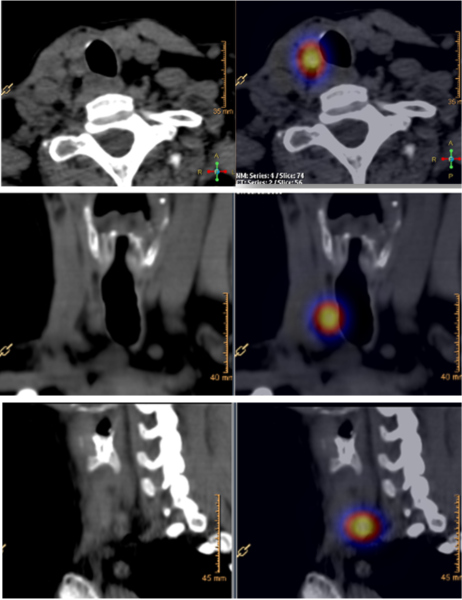

Las figs 2-5 ilustran casos de la serie analizada.